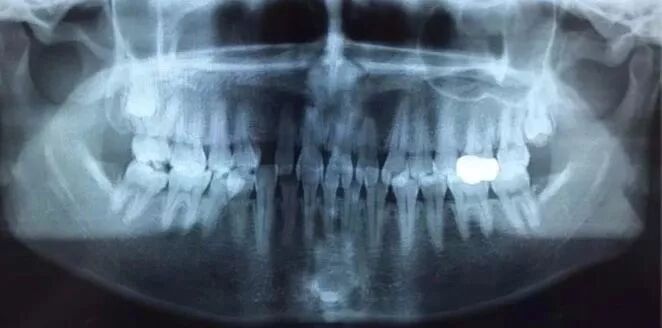

全景片曲面断层片

此片意义极大,甚至有时候高于第一张!因为我们可以通过看侧脸来大致判断第一张片子的某些数据,但是如果不拍曲断什么的 ,谁也没办法保证下面有没有肿瘤什么的埋伏牙,囊肿,高钙化骨结节,牙根吸收,根折,甚至恶性肿瘤,医生不拍这个片子,说白了就是给自己埋炸弹,如果看牙过程中发现牙齿出现什么问题,在做之前没发现这些隐患,属于不负责的做法。

万一有恶性肿瘤呢?虽然概率极低,但医学从不开玩笑,没有是0,有就是百分之百,为了您生命着想,拍片并不是为了赚您的钱!